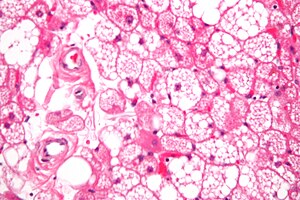

Micrograph of a hibernoma, a tumour thought to arise from brown fat. H&E stain.